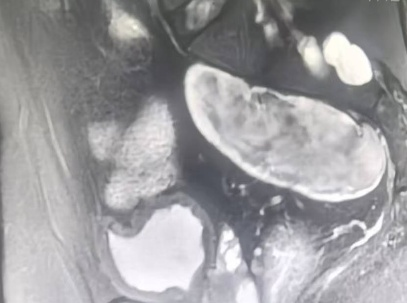

之后王志东教授团队又接诊一名60多岁的反复上腹隐痛来就诊的患者,外院上腹部彩超怀疑胰体尾占位。经腹部增强CT、肿瘤标志物检测及穿刺活检等检查,确诊为胰腺体部中分化腺癌。患者对术后生活质量有较高渴望,要求尽可能保留脾脏,如何在完整切除肿瘤的基础上保留脾脏,成为诊疗团队面临的核心挑战。

胰腺位于人体上腹部的深面,被胃肠、血管等脏器环绕,解剖结构较复杂,而胰体尾部癌因位置特殊,毗邻脾动静脉等重要血管,常常需要联合切除脾脏,而保留脾脏手术难度更是大幅提升。脾脏作为人体重要的免疫器官,承担着免疫防御、造血储血等关键功能,切除后增加术后感染、血小板升高致血栓、术后免疫力下降等并发症风险,影响患者近期、远期的生活质量。王志东教授团队术前反复研读影像学资料,精准评估肿瘤浸润范围、与脾动静脉的毗邻关系,逐一排查术中可能出现大出血、脾梗死、肿瘤残留等潜在风险,敲定个性化腹腔镜微创保脾手术方案,采用“保留脾动静脉的胰体尾切除术”(Kimura法)。

手术当天,麻醉团队完成精准麻醉,为手术全程保驾护航。王志东教授带领团队李运浩博士、金鑫医师,通过腹部5个“钥匙孔”大小的微小切口建立操作通道,借助腹腔镜高清放大视野,清晰呈现胰腺病灶、脾动静脉及周围脏器的解剖结构,精准避开重要血管与神经。手术中,团队如同在“刀尖上跳舞”般,用精细的操作分离胰体尾部与脾脏的粘连,仔细结扎胰腺滋养血管,在确保肿瘤完整切除的前提下,精准保护脾动静脉血供,避免脾脏缺血坏死,全程出血控制精准。经过数小时的精准攻坚,最终成功切除胰腺体尾部病灶,完整保留脾脏,手术顺利,术后恢复良好出院。